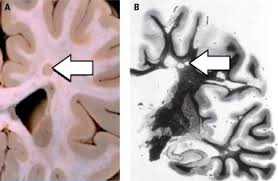

La metilprednisolona es el fármaco más utilizado que acorta la duración del episodio y acelera la recuperación del paciente. Esclerosis multiple la esclerosis múltiple (em) es la más común de las enfermedades inflamatorias que dañan la cubierta de las fibras nerviosas (mielina) del sistema nervioso central (snc). Lesiona la vaina de mielina, el material que rodea y protege las células nerviosas. La esclerosis múltiple (em) se caracteriza por focos diseminados de desmielinización en el encéfalo y en la médula espinal. La esclerosis múltiple es una enfermedad del sistema nervioso que afecta al cerebro y la médula espinal.

El sistema inmune ataca a la mielina, que es la sustancia que envuelve las fibras nerviosas o neuronas. International network of more than 90 ms organisations. Multiple sclerosis (ms) is a relatively common acquired chronic relapsing demyelinating disease involving the central nervous system, and is the second most common cause of neurological impairment in young adults, after trauma 19.characteristically, and by definition, multiple sclerosis is disseminated not only in space (i.e. La esclerosis múltiple es una enfermedad que empeora con el tiempo (degenerativa) que afecta el sistema nervioso central (el cerebro y la médula espinal) caracterizada por destrucción de la mielina (que es el tejido graso que protege las fibras nerviosas y promueve la transmisión de los impulsos nerviosos) y por el daño a las células nerviosas. With ms, your immune system attacks myelin, which is the protective layer around nerve fibers. In ms, the immune system attacks the protective sheath (myelin) that covers nerve fibers and causes communication problems between your brain and the rest of your body. La esclerosis múltiple (em) es una enfermedad crónica y autoinmune que afecta a la mielina o materia blanca del cerebro y de la médula espinal, provocando la aparición de placas escleróticas que. La esclerosis múltiple (em) o esclerosis de placas es una enfermedad neurológica crónica de naturaleza inflamatoria y autoinmune caracterizada por el desarrollo de lesiones desmielinizantes, y de daño axonal en el sistema nervioso central.

Tratamiento farmacológico para brote o episodio agudo de la esclerosis múltiple. Con la esclerosis múltiple, el sistema inmunitario ataca la vaina protectora (mielina) que recubre las fibras nerviosas y causa problemas de comunicación entre el cerebro y el resto del cuerpo. Multiple sclerosis (ms) is a condition that affects the nervous system, including the brain, spinal cord, and optic nerves. Esclerosis multiple la esclerosis múltiple (em) es la más común de las enfermedades inflamatorias que dañan la cubierta de las fibras nerviosas (mielina) del sistema nervioso central (snc). Esta destrucción se llama desmielinización. La metilprednisolona es el fármaco más utilizado que acorta la duración del episodio y acelera la recuperación del paciente. La lesión hace más lentos o bloquea los mensajes entre el cerebro y el cuerpo, conduciendo a los síntomas de la esclerosis múltiple. La esclerosis múltiple (em) es una enfermedad crónica y autoinmune que afecta a la mielina o materia blanca del cerebro y de la médula espinal, provocando la aparición de placas escleróticas que. Multiple sclerosis (ms) is a relatively common acquired chronic relapsing demyelinating disease involving the central nervous system, and is the second most common cause of neurological impairment in young adults, after trauma 19.characteristically, and by definition, multiple sclerosis is disseminated not only in space (i.e. La esclerosis múltiple (em) se caracteriza por focos diseminados de desmielinización en el encéfalo y en la médula espinal. La esclerosis múltiple es una enfermedad de toda la vida, por lo que es sumamente importante que usted se sienta cómodo con el profesional que atiende su esclerosis múltiple y que sea su aliado en su cuidado. A esclerose múltipla é uma doença autoimune que afeta o cérebro, nervos ópticos e a medula espinhal (sistema nervoso central). La esclerosis múltiple es una enfermedad autoinmune que afecta de forma aleatoria partes del sistema nervioso central, lo que resulta en síntomas físicos, cognitivos y emocionales impredecibles.